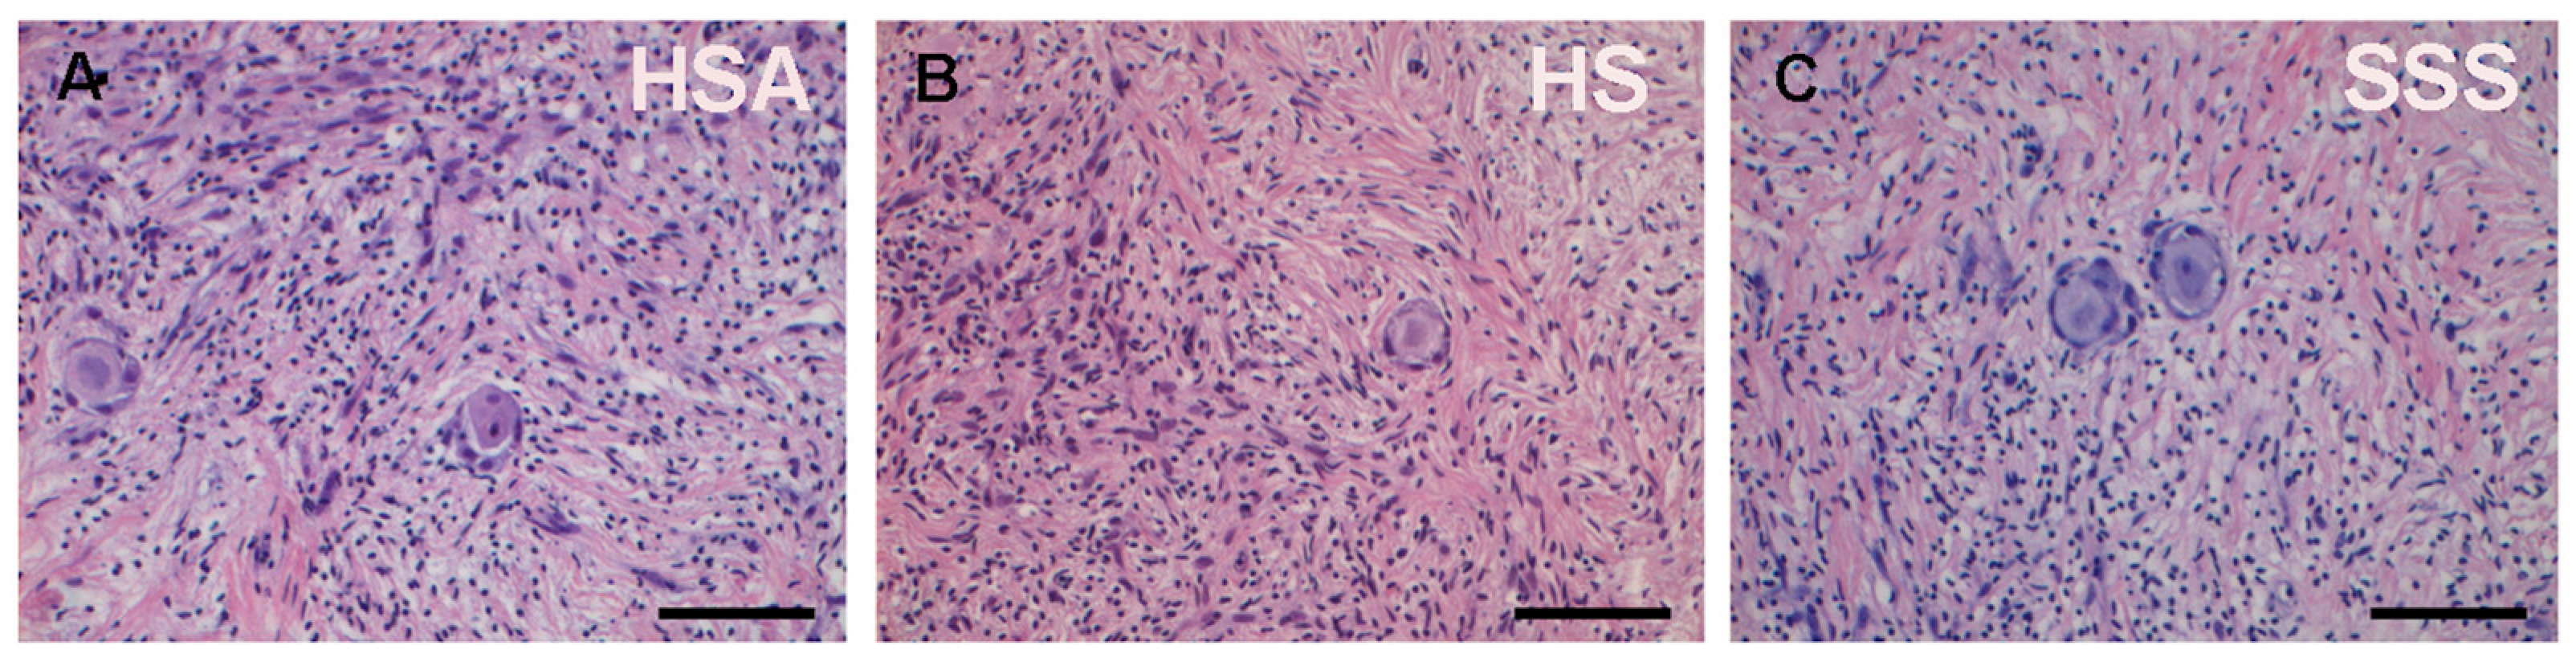

| HSA | Human Serum Albumin |

| HS | Human Serum |

| SSS | Serum Substitute Supplement |